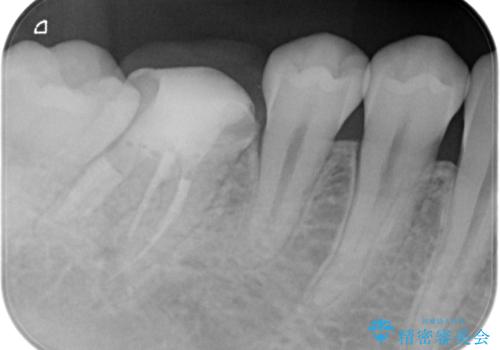

- 奥歯の治療の継続を主訴に来院された患者様です。

他院にて根管治療を行ったそうですが、ラバーダムを使用していなかったため、クラウン修復の前に当院の治療を希望され受診されました。

根管内に充填されている材料は、スカスカの状態で簡単に除去ができました。

術後1年経過を見ていますが、問題なく良好な経過をたどっています。